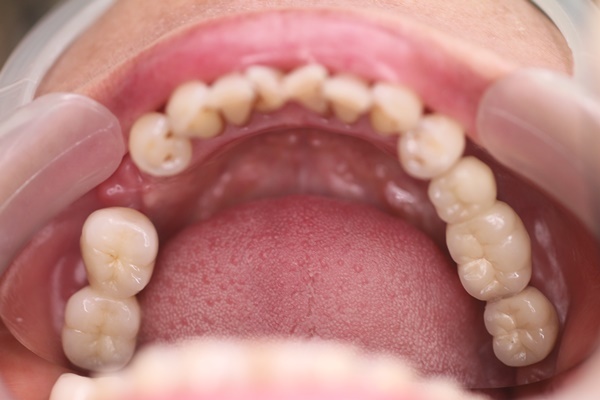

先秀一下我的一口爛牙。

不要說你的有多糟糕,看看我的肯定安慰不少。至於為什麼少成這樣才想要去植牙?